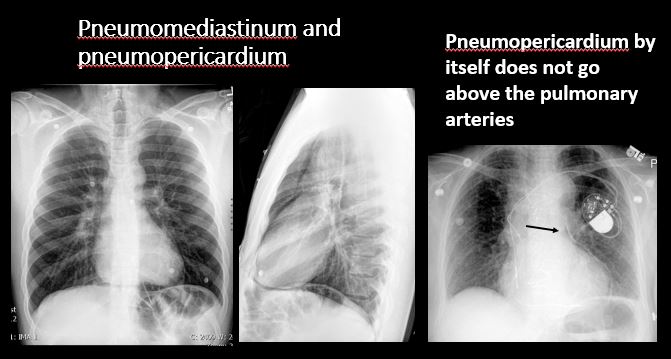

There is pneumomediastinum and/or pneumopericardium. [Yes/No]